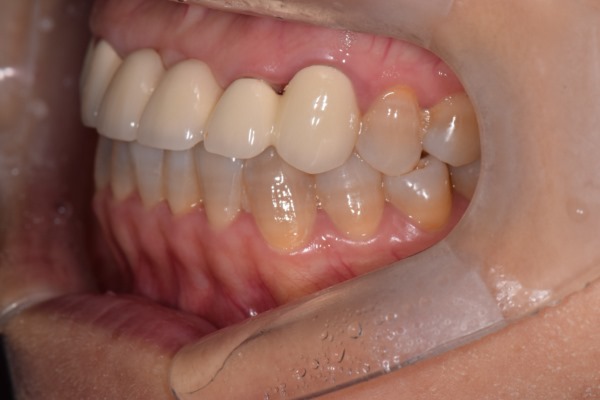

옆모습 사진이에요. 조금 흔들렸네요.

진료실용 DSLR로 다시 한번 촬영했습니다. 측면에서 다시 보니 치아가 앞으로 뻗으러져 보이기도 하네요.